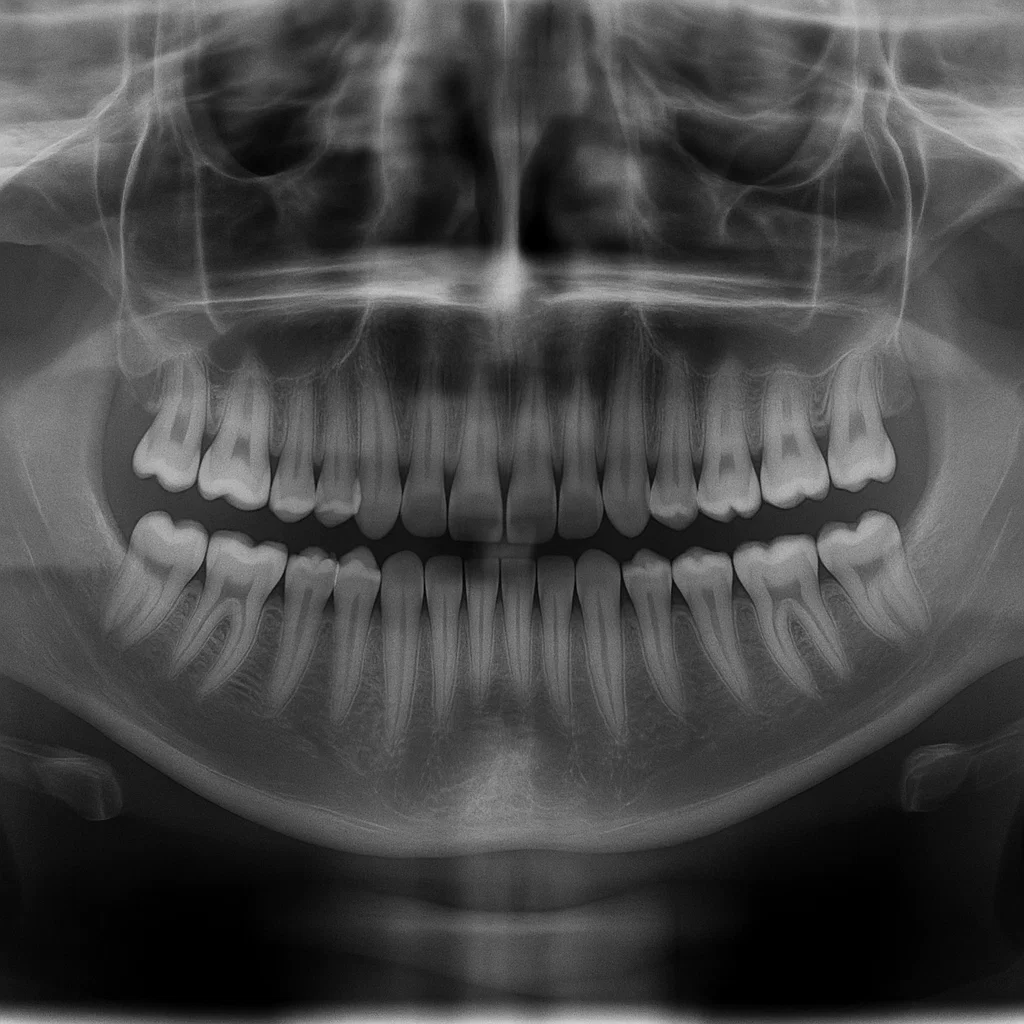

- 초진 환자로 파노라마 엑스레이 촬영 등 진단이 필요한 경우

Q8. 스케일링은 치과의사가 직접 하나요?

대부분의 경우 스케일링 시술은 치과위생사가 시행하고, 치과의사는 최종 확인을 담당합니다.

이는 의료법상 허용된 보조 진료 행위로, 자격을 갖춘 치과위생사가 치석 제거, 잇몸 관리 등의 시술을 안전하게 시행합니다.

물론 진단과 보험 청구, 치주 질환 여부 판단은 반드시 치과의사의 지시에 따라 이뤄지며,

필요시 치과의사가 직접 스케일링을 하거나 중간에 교체하는 경우도 있습니다.